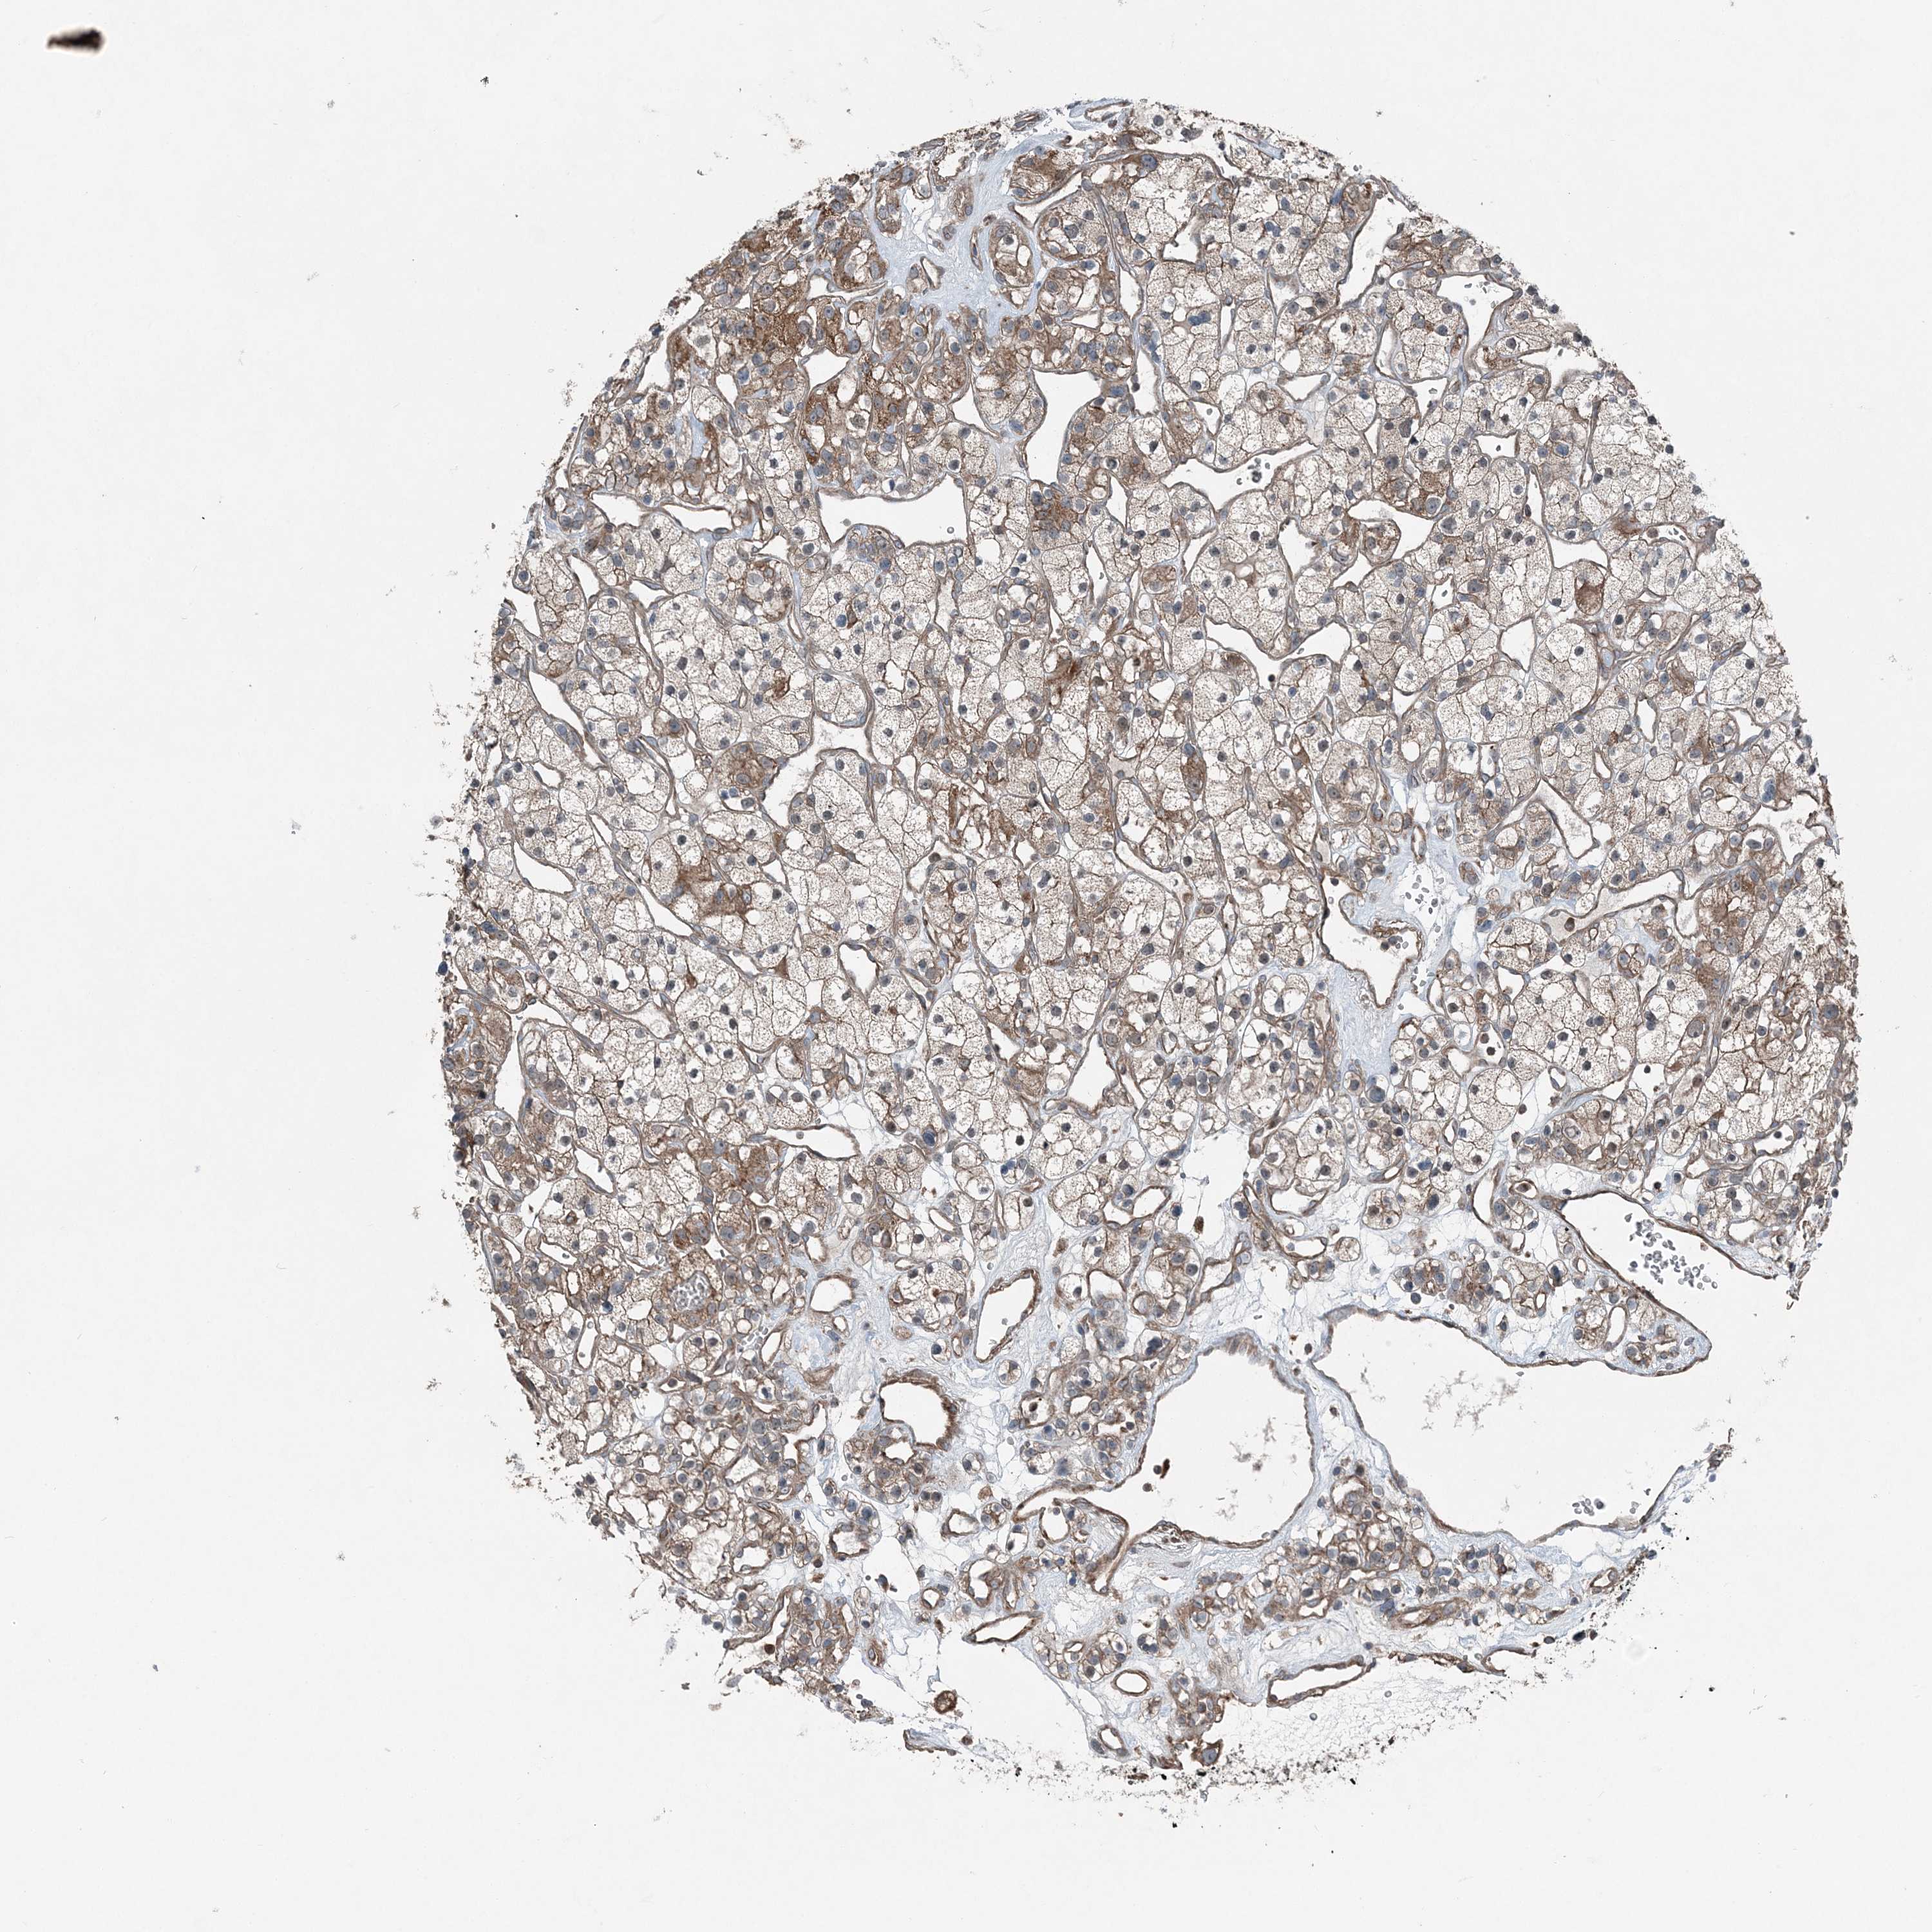

KIDNEY RENAL PAPILLARY CELL CARCINOMA (TCGA) - Interactive survival scatter ploti

The Survival Scatter plot shows the clinical status (i.e. dead or alive) for all individuals in the patient cohort, based on the same data that underlies the corresponding Kaplan-Meier plots. Patients that are alive at last time for follow-up are shown in blue and patients who have died during the study are shown in red.

The x-axis shows the expression levels (FPKM) of the investigated gene in the tumor tissue at the time of diagnosis. The y-axis shows the follow-up time after diagnosis (years). Both axes are complimented with kernel density curves demonstrating the data density over the axes. The top density plot shows the expression levels (FPKM) distribution among dead (red) and alive patients (blue). The right density plot shows the data density of the survived years of dead patients with high and low expression levels respectively, stratified using the cutoff indicated by the vertical dashed line through the Survival Scatter plot. This cutoff is automatically defined based on the FPKM cutoff that minimizes the p-score. The cutoff can be changed by dragging the vertical line or by entering a cutoff value in the square labeled "Current cut-off".

Under the Survival Scatter plot the p-score landscape (black curve; left axis) is shown together with dead median separation (red curve; right axis). Dead median separation is the difference in median mRNA expression between patients who have died with high and low expression, respectively. It is calculated as follows: median FPKM expression of dead patients with high expression - median FPKM expression of dead patients with low expression. This is intended to aid the user in visually exploring custom cutoffs and the associated p-scores and dead median separation.

Individual patient data is displayed and can be filtered by clicking on one or more of the category buttons on the top of the page. Categories describing expression level and patient information include: high, low, alive, dead, female, male and tumor stages. The scale of the x-axis can be toggled between linear and log-scale by clicking on the "x log" button. Mouse-over function shows TCGA ID, patient information and mRNA expression (FPKM) for each patient.

& Survival analysisi

Kaplan-Meier plots summarize results from analysis of correlation between mRNA expression level and patient survival. Patients were divided based on level of expression into one of the two groups "low" (under cut off) or "high" (over cut off). X-axis shows time for survival (years) and y-axis shows the probability of survival, where 1.0 corresponds to 100 percent.

KY is not prognostic in Kidney Renal Papillary Cell Carcinoma (TCGA)